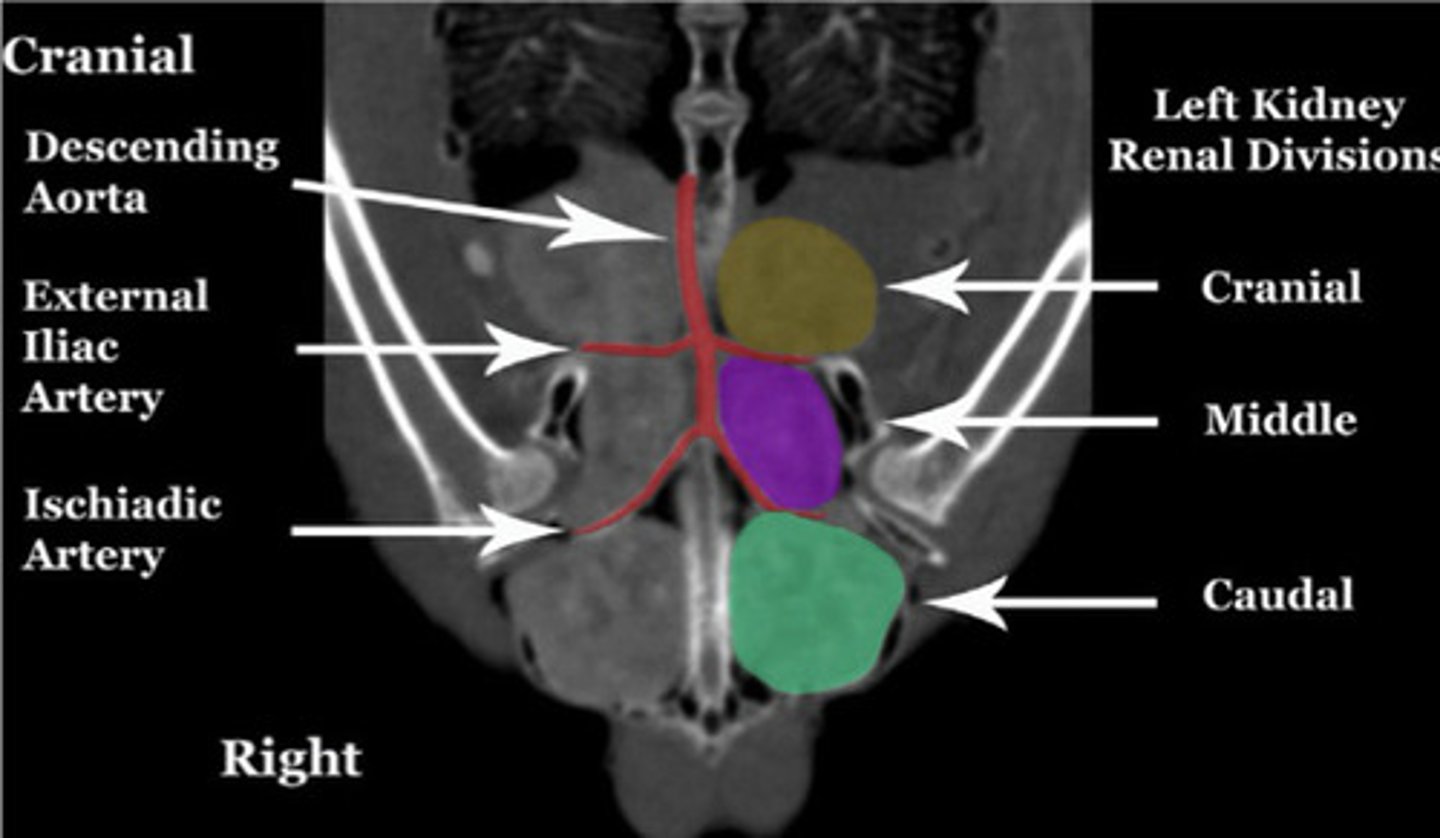

Bird kidneys are composed of (one/several) lobe(s)

Why is US'ing them difficult?

What types of nephrons do they have and what % do they make up?

Is their urine concentrated?

Urates from reptilian-type nephrons, Urine from mammalian-type nephrons

Where are urates produced? Where is urine produced?